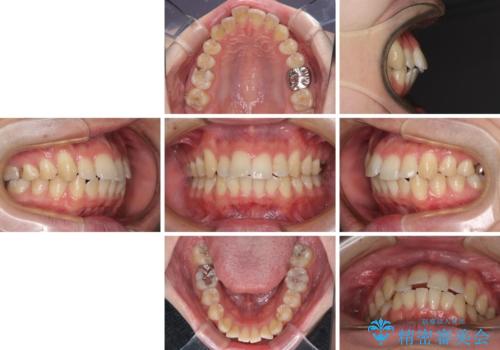

- 上下前歯のデコボコを気にして来院された患者様です。

マウスピース矯正でもワイヤー矯正でも対応可能でしたが、インビザラインによる自己管理が煩わしいとのことで、ワイヤー装置にて矯正治療を行うこととしました。

口元はやや突出感がありましたが抜歯矯正をするほどではないため、舌突出癖を改善するトレーニングをしっかりと行っていただき、現在よりも唇が閉じやすい位置に仕上げていくこととしました。

下顎前歯が思っていた以上に動きが悪く、想定よりも期間がかかってしまいました。

矯正治療後には気になっていた銀歯をセラミックで自然な色に仕上げました。